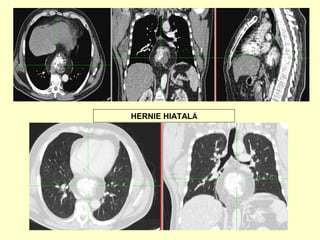

HERNIE HIATALĂ

hernie hiatală voluminoasă care

conţine şi o mare parte din corpul

gastric, înconjurată de o importantă

cantitate de grăsime abdominală